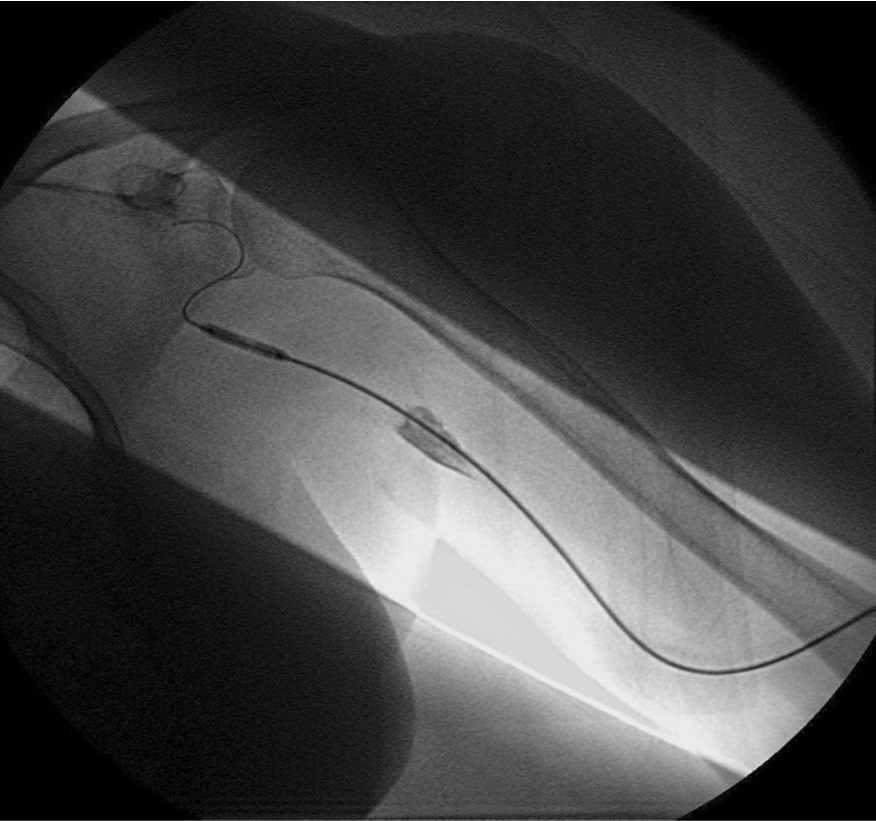

환자의 AV fistula는 초음파상 total thrombotic occlusion 된 상태였으며 시술 전 urokinase 100000 unit를 사용하여 thrombolysis and aspirated thrombectomy를 시행하였다. 그 후 시행한 shuntogram(Fig. 1) 상 left basilic vein 의 total ocdusion을 보이며 초음파상 remant vein의 크기는 1mm 이하로 확인되었다. 투시하에서 확인되는 outflow vein은 없었기에 초음파 유도하에 5 Fr Kumpe catheter(Soft-Vu, AngioDynamics, USA, NY) 에 0.035’ straight-tip guide wire(Terumo, Tokyo, Japan)를 사용하여 막힌 left basilic vein으로 15cm 이상 진행하였으며(Fig. 3), 4mm balloon (synergy, Boston, Ireland)를 사용하여 blind angioplasty를 하며 true lumen으로의 진행을 시도하였으나 실패하였다(Fig. 4). 더 이상의 antegrade로의 접근은 어려울 것으로 판단하여 regrograde approach를 위하여 left internal jugular vein 을 초음파 유도하에 9Fr sheath( Accu-Sheath, Sungwonmedical, Korea, Cheongju)을 사용하여 access 하였다. (Fig. 5A) 그리고 5Fr Cobra & sherpherd hook catheter (A&A M.D., Korea, Sungnam) 를 이용하여 left axillary vein으로의 접근을 시도하였다(Fig. 5B).

Fig. 5.

A-B. Retrograde guide wire negotiation to left basilica vein via transjugular approach